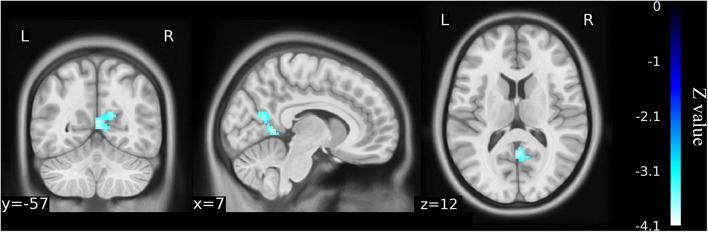

This study aimed to investigate the brain functional alterations with resting-state functional magnetic resonance imaging (rs-fMRI) in older patients with knee osteoarthritis (KOA) before and after total knee arthroplasty (TKA) and to assess the causal relationship of the brain function and neuropsychological changes. We performed rs-fMRI to investigate brain function of 23 patients aged ≥65 with KOA and 23 healthy matched controls. Of the KOA patients, 15 completed postoperative rs-fMRI examinations. Analyzes of the amplitude of low-frequency fluctuation (ALFF) and functional connectivity (FC) were used to estimate differences in brain functional parameters between KOA patients, postoperative patients, and the controls. The relationship between changes of pre- and post-surgical status in ALFF and neuropsychological test results was analyzed. Compared with the controls, all patients with KOA exhibited decreased ALFF in the default mode network (bilateral angular gyrus, precuneus gyrus, medial superior frontal gyrus) and increased ALFF in the bilateral amygdala and cerebellum posterior lobe before surgery ( < 0.001). Altered ALFF persisted in the same brain regions 1 week postoperatively. The decreased ALFF in the left precuneus gyrus and middle temporal gyrus was found after surgery when compared with preoperative data ( < 0.01). Preoperatively, the KOA patients exhibited increased FC between the left precuneus gyrus and the right supplementary motor area compared to the controls ( < 0.001), but this connectivity became no significant difference after TKA. The left Cerebelum_9 was found to have decreased FC with the right precuneus gyrus postoperatively ( < 0.001) although this was not significantly different before surgery. The significantly altered ALFF values were not correlated with changes in cognitive assessment scores. In older patients with end-stage KOA, functional alterations in important brain regions were detected with the persistence and further changes observed at an early stage after knee replacement. Our data further our understanding of brain functional abnormalities and cognitive impairment in older patients following knee replacement, which may provide therapeutic targets for preventive/treatment strategy to be developed. Clinical Trial Registration: http://www.chictr.org.cn/index.aspx, ChiCTR1800016437; Registered June 1, 2018.

本研究旨在通过静息态功能磁共振成像(rs-fMRI)调查老年膝骨关节炎(KOA)患者全膝关节置换术(TKA)前后的脑功能改变,并评估脑功能与神经心理变化之间的因果关系。我们对23例年龄≥65岁的KOA患者及23名匹配的健康对照者进行rs-fMRI以研究脑功能。其中15例KOA患者完成了术后rs-fMRI检查。采用低频振幅(ALFF)分析和功能连接(FC)分析来评估KOA患者、术后患者及对照者之间脑功能参数的差异。分析了手术前后ALFF变化与神经心理测试结果之间的关系。与对照组相比,所有KOA患者术前默认模式网络(双侧角回、楔前回、额上回中部)的ALFF均降低,双侧杏仁核和小脑后叶的ALFF增加(<0.001)。术后1周,相同脑区的ALFF改变持续存在。与术前数据相比,术后发现左侧楔前回和颞中回的ALFF降低(<0.01)。术前,与对照组相比,KOA患者左侧楔前回与右侧辅助运动区之间的FC增加(<0.001),但TKA术后这种连接性无显著差异。术后发现左侧小脑_9与右侧楔前回的FC降低(<0.001),尽管术前无显著差异。ALFF值的显著改变与认知评估评分的变化无关。在老年终末期KOA患者中,检测到重要脑区的功能改变,且在膝关节置换术后早期观察到这些改变持续存在并进一步变化。我们的数据进一步加深了我们对老年患者膝关节置换后脑功能异常和认知障碍的理解可能为制定预防/治疗策略提供治疗靶点。临床试验注册:http://www.chictr.org.cn/index.aspx,ChiCTR1800016437;2018年6月1日注册。